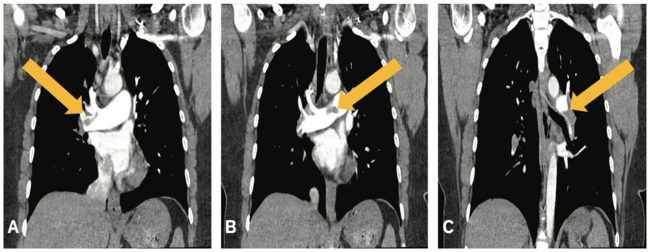

An electrocardiogram (ECG) revealed sinus tachycardia with normal blood pressure (121/77 mmHg). There were no other remarkable findings on physical assessment. The patient underwent a chest computed tomography angiogram (CTA) to rule out PE. CTA revealed extensive, acute, nonocclusive saddle PE involving the bilateral main, lobar, segmental, and subsegmental pulmonary artery (PA) divisions (Figure 1). The right ventricle (RV) was dilated with straightening of the interventricular septum and the RV/left ventricular (LV) ratio was 1.57. The main PA was also slightly dilated at 3.1 cm, suggesting right heart strain. Small, patchy, subpleural ground-glass opacities were observed in the lungs and associated with SARS-CoV-2 pneumonia.